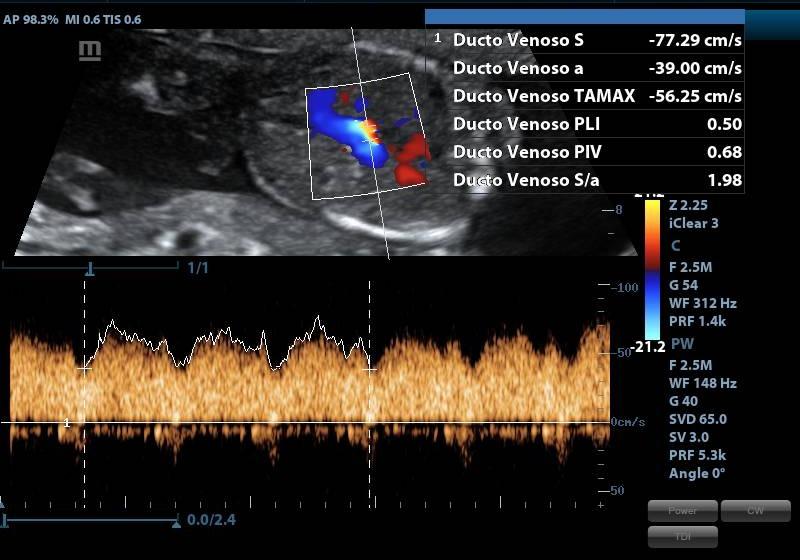

ESPECIFICACIONESLONGITUD DEL FETO CORONOCAUDAL (LCC) LIQUIDO AMNIOTICO FRECUENCIA CARDIACA FETAL (LCF) DESCARTAR CROMOSOMOPATIAS MEDICION TRANSLUCENCIA NUCAL (TN) PRESENCIA Y MEDICION DE HUESO NASAL ANGULO MAXILOFACIAL PARTES FETALES DIAFRAGMA EVALUACION CAMARA CARDIACA EVALUACION COLUMNA VERTEBRAL FLUJOMETRIA DOPPLER ARTERIAS UTERINAS (PREVENTOR PREECLAMPSIA) DUCTUS VENOSO UBICACIÓN DE PLACENTA, DESCARTAR HEMATOMAS O DESPRENDIIENTOS INSERCION DE CORDON UMBILICAL

ESPECIFICACIONESSE ESTUDIA: BIOMETRIA FETAL DIAMETRO BIPARIETAL (DBP) CIRCUNFERENCIA CEFALICA (CC) CIRCUNFERENCIA ABDOMINAL (CA) LONGITUD DE FEMUR (LF) SITUACION Y POSICION FETAL UBICACIÓN Y MADUREZ DE PLACENTA CANTIDAD DE LIQUIDO AMNIOTICO (ILA) SEMANAS DE GESTACION PESO FETAL SEXO FRECUENCIA CARDIACA FETAL (LCF) OBSERVACION MOVIIENTO FETAL FLUJOMETRIA DOPPLER ARTERIAS UTERINAS (PREVENTOR PREECLAMPSIA) ARTERIA CEREBRAL MEDIA (ACM) ARTERIA UMBILICAL RELACION CEREBROPLACENTARIA. DUCTUS VENOSO